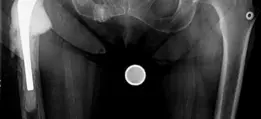

الأشعة السينية (X-rays):

- تُعد الأشعة السينية القياسية (AP للحوض، جانبية للورك) هي الخطوة الأولى.

- توفر تقييمًا أوليًا لوضع المفصل الصناعي، ومدى تآكله، وأي علامات على فقدان العظام أو ارتخاء المكونات.

- يمكن أن تظهر الأشعة السينية أيضًا أي كسور أو انقطاع في عظم الحوض.